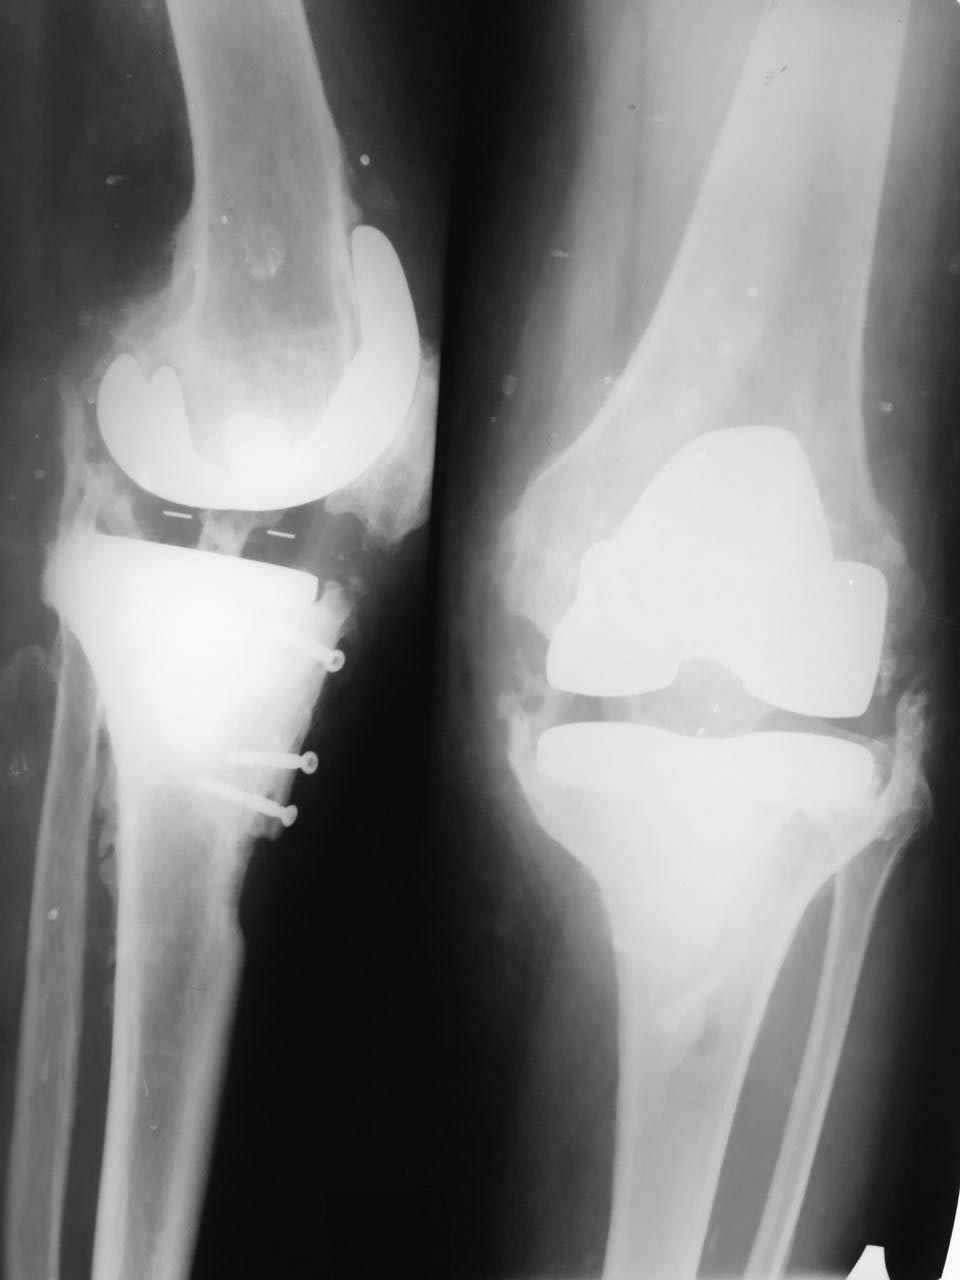

Рецидивирующие экзофиты после ТЭКС

Всем здравствуйте! Подскажите тактику, кто сталкивался с таким явлением.. Протез стоит 10 лет, болей нет, но постоянно растут экзофиты.

Уже удаляли экзофиты 2 раза с хорошим, но временным эффектом. Сейчас опять движения качательные.

хотелось бы больше информации- почему большеберцовый компонент установлен в варусе, почему выбран данный размер компонентов ( есть ощущение, что маловаты для данного сустава), какие задачи решались остеотомией большеберцовой бугристости- низкое/высокое стояние надколенника или устранение контрактуры?